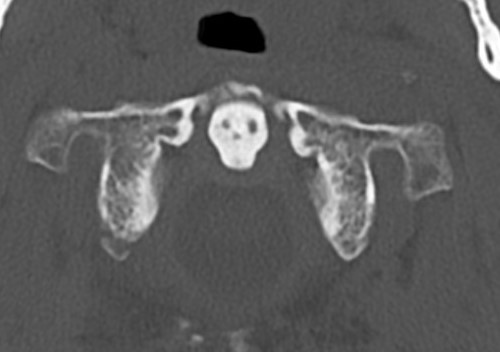

CT

Better defines displacement, ADI, LMD and bony avulsions of the transverse ligament

CT LMDCT Jefferson